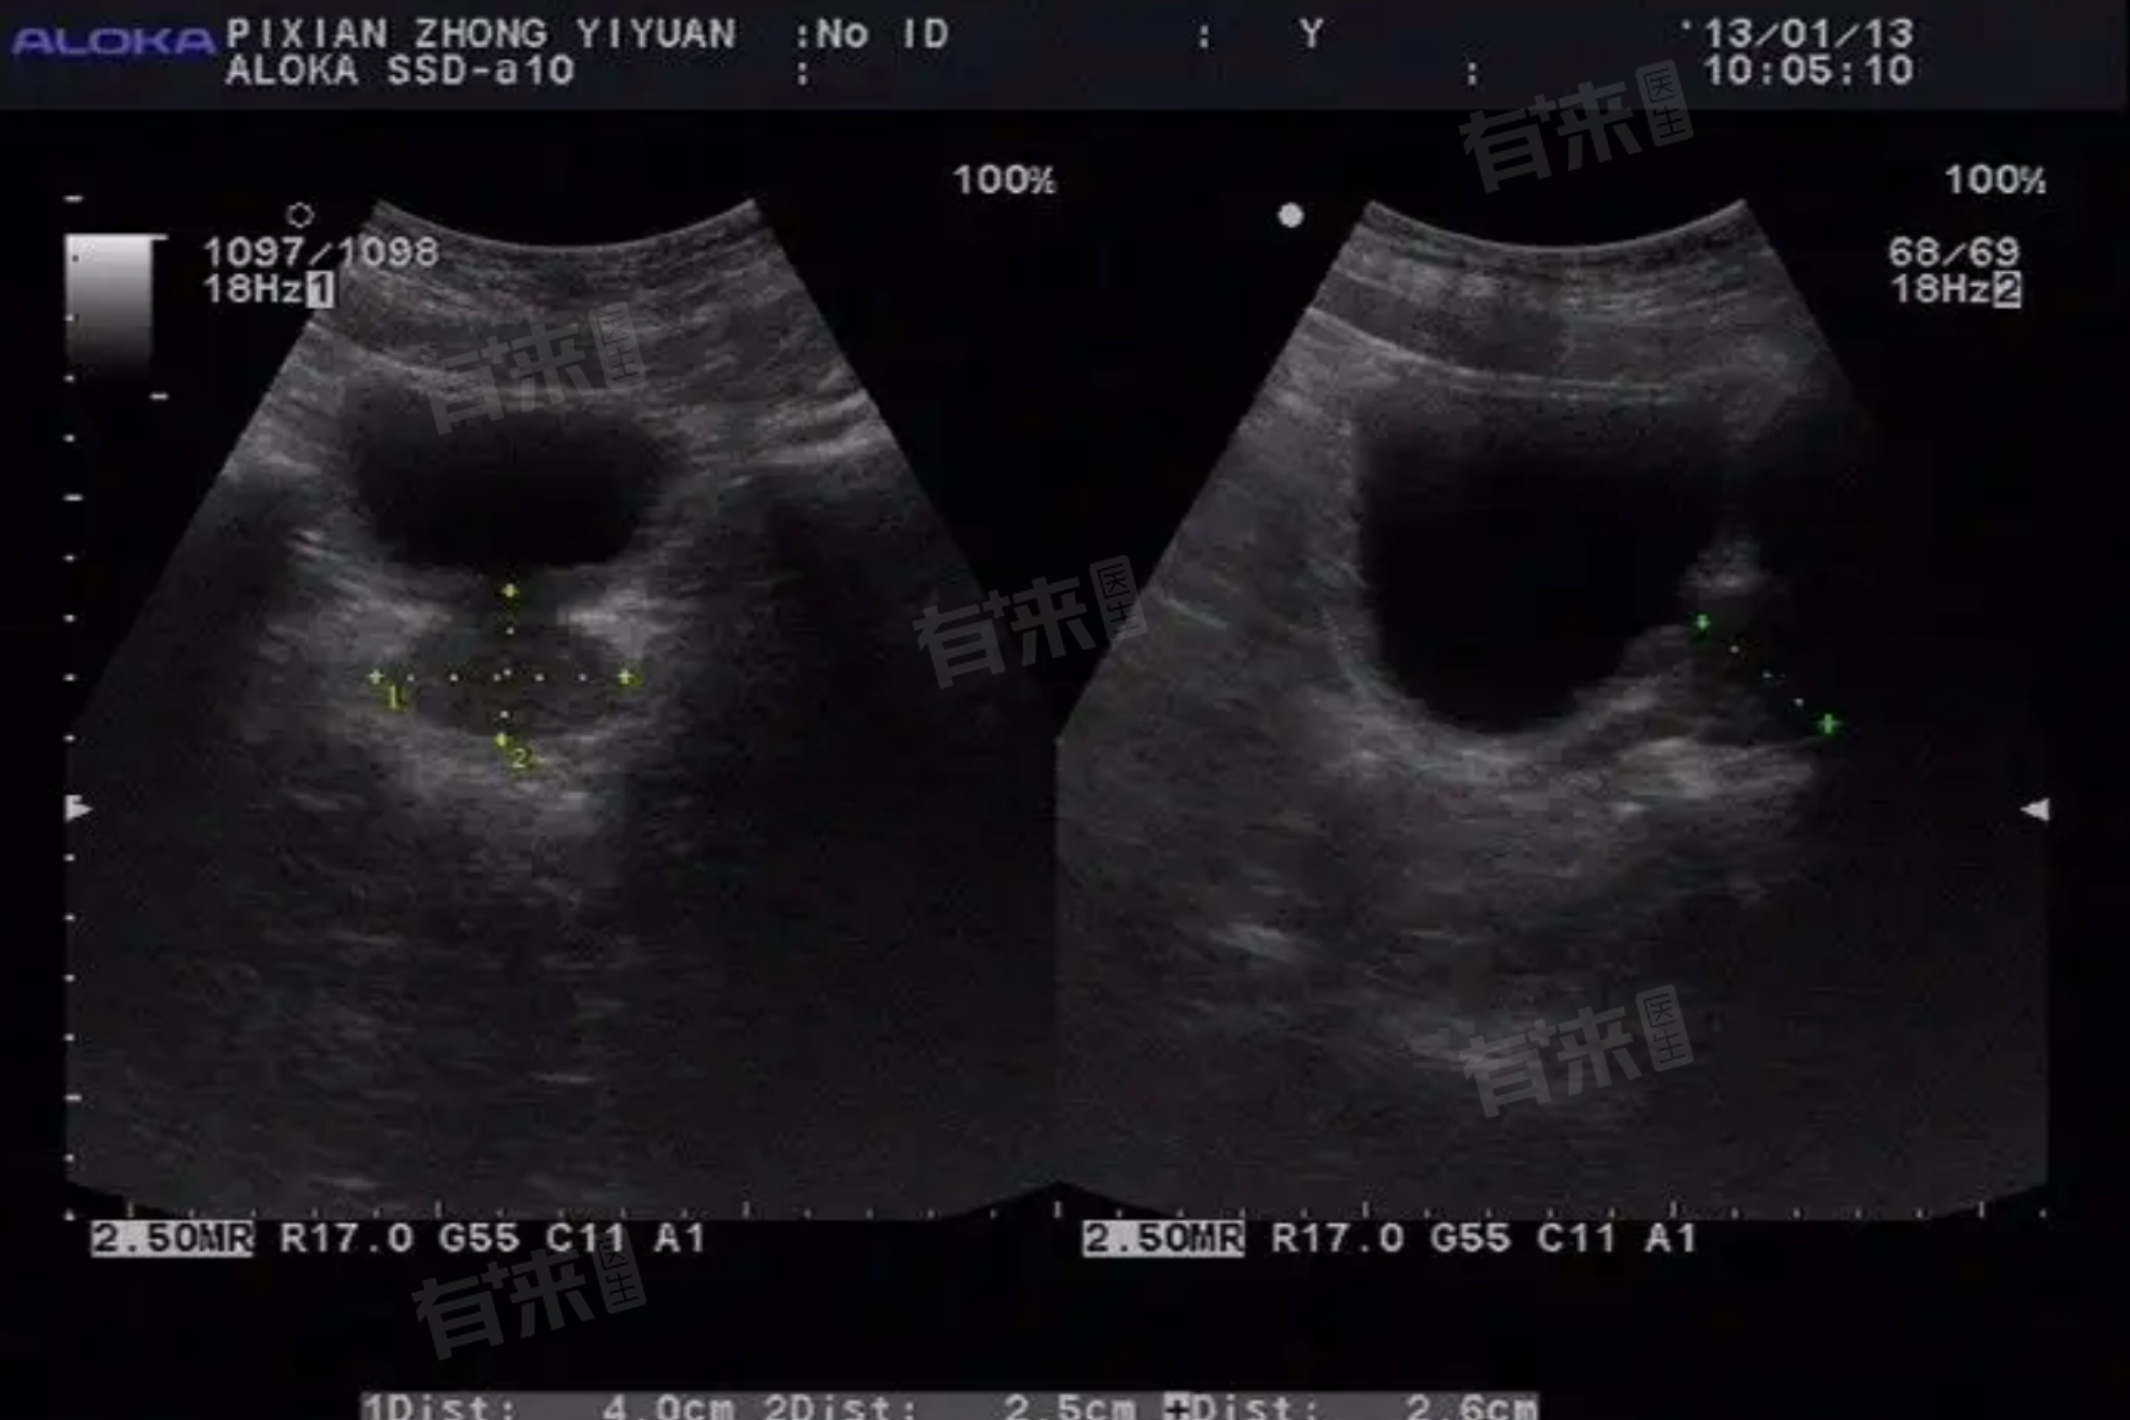

前列腺位于膀胱的下方,膀胱是空腔脏器。当憋尿时膀胱处于充盈状态,使得前列腺的结构在B超下能够更清晰地显示出来。充盈的膀胱可以作为良好的透声窗,使得超声波能够更顺利地穿透并反射回前列腺的图像,从而提高图像的清晰度和诊断的准确性。

憋尿后进行的前列腺彩超可以用于观察前列腺的大小、形态和内部结构,还可以辅助诊断多种前列腺疾病,如前列腺增生、前列腺肿瘤、前列腺囊肿等,疾病的诊断依赖于对前列腺结构的清晰观察和分析。